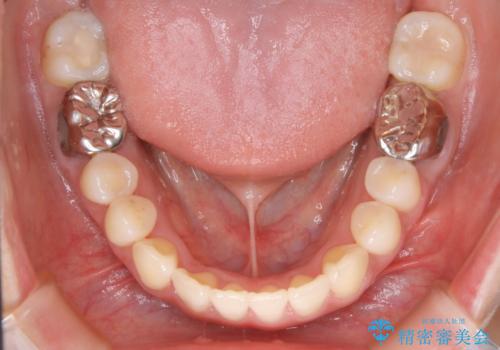

【非抜歯】インビザライン 隠れた前歯を並べる矯正治療

- 前歯のガタつき・奥に隠れてしまっている歯の矯正治療を希望されて初診来院されました。

顔貌的に口元を下げたいといった希望はなく抜歯はなるべく避けたいとのご要望からマウスピース装置(インビザライン)での治療を行うこととなりました。

非抜歯で矯正を行う場合にガタつきの改善に必要なスペースを作るために歯の遠心移動を行います。

最初の位置から奥に歯を移動させていくことで前歯のガタつきを改善したり、前歯の位置を後方に移動させることが可能となります。